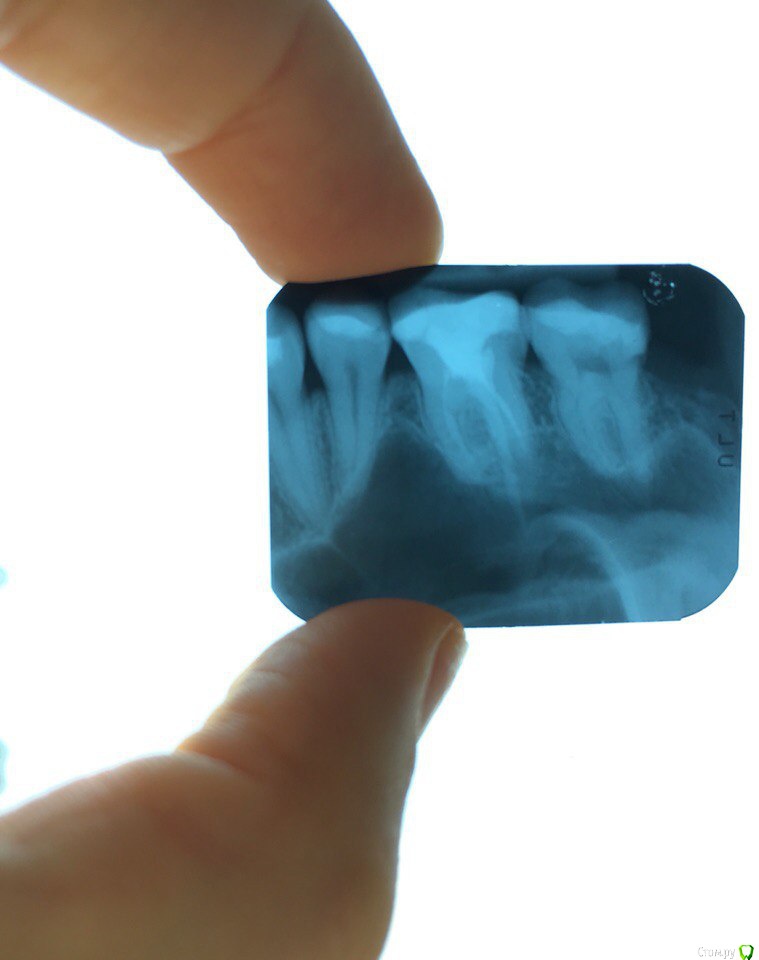

Lana_x Опубликовано 19 марта, 2016 Поделиться Опубликовано 19 марта, 2016 (изменено) Здравствуйте,Уважаемые Врачи! 20 ноября была травма последнего зуба на верхней челюсти с левой стороны. Сын когда вставал, ударил головой в мою нижнию челюсть, зуб сломался и посредине зуба был как-будто осколок. 21 ноября часть зуба удалили, десну зашили. (врач назначил антибиотики курсом 7 дней, пить не стала, тк. в последнее время очень много их принимала). 4 декабря поставили пломбу25 марта пломба отвалиласьпоставили новую, когда ставили было очень больно( обезбаливающее не делали. Сейчас беспокоит боль в зубе когда надавливаю или прикусываю зуб. щетку, если дотронутся чем-то жестким до зуба, именно в месте где он сломался (стоит пломба) очень больно. Боль на 10 из 10, но если не трогать зуб не беспокоит, температура 37-37.2 периодически поднимается. С левой стороны, где был сломан зуб, боль отдает в ухо (лор сказал с ухом все нормально), заложенность носа, слизь по задней стенке стекает, небольшое воспаление в носоглотке. С 20 января - 20 февраля лечила двухсторонний гайморит (антибиотики месяц, пункция двухсторонняя, промывание пазух в течение недели). КТ подтверждает, что лечение прошло успешно. Скажите пожалуйста может быть проблема в зубе? Отдавать болью в ухо, давать температуру и выделение слизи из носоглотки? Была на приеме у стоматолога (молоденькая девочка), на снимке не увидела ничего странного, но зуб то болит(((((( на 80% уверена, что мои проблемы связанные с отоларингологией из-за зуба. Может быть пульпит или еще что-нибудь? Кроме рентгена какое можно еще обследование пройти? Заранее всем благодарна за ответ. Изменено 19 марта, 2016 пользователем Lana_x Ссылка на комментарий

DmitrySH Опубликовано 19 марта, 2016 Поделиться Опубликовано 19 марта, 2016 Сделать КТ.Вокруг верхушек 6-го зуба не все спокойно, но на снимке тяжело разобрать.Тест на витальность 7-го зуба. Ссылка на комментарий